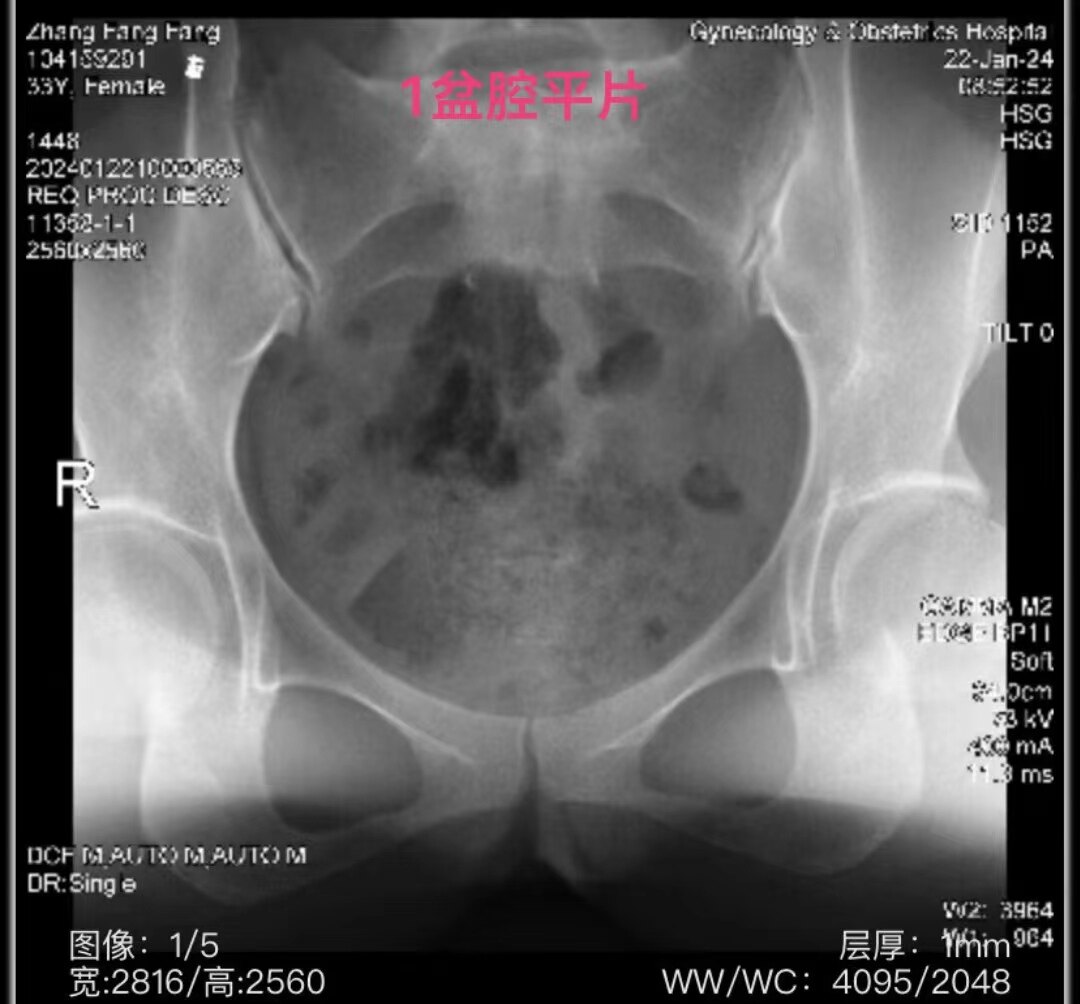

这是一例在大学附属妇产医院做的碘油子宫输卵管造影,最后的诊断:双侧输卵管通而极不畅,建议SSG。我看了这五张造影片后发现,造影管前端堵塞宫颈内口不严实,有较多造影剂反流回到阴道,注入到宫腔内的造影剂不够,子宫腔和输卵管内造影剂不能继续充盈,造成输卵管远段未见显影。但是,拔掉造影管2小时后(常规碘油是24小时)拍弥散相,盆腔内,尤其是双侧输卵管伞部周围可见造影剂弥散,以左侧明显,说明双侧输卵管都是通的。本来,拔掉造影管后,输卵管内没有造影剂继续注入,管内压力减低,造影剂能从伞端溢出至盆腔,说明双侧输卵管基本通畅。因此,造影时应该造影管前端更紧密地顶住宫颈外口,继续再多注入2毫升碘油,看到伞端有造影剂溢出时再拔掉造影管。因此,这个造影报告最后,不应该建议做SSG(选择行输卵管造影),而是再多注入2毫升造影剂。

拔掉造影管2小时后延迟弥散相片:双侧输卵管伞部周围可见造影剂弥散,以左侧明显。因为盆腔有少量液体,碘油在盆腔左侧呈多小个圆形聚集在一起